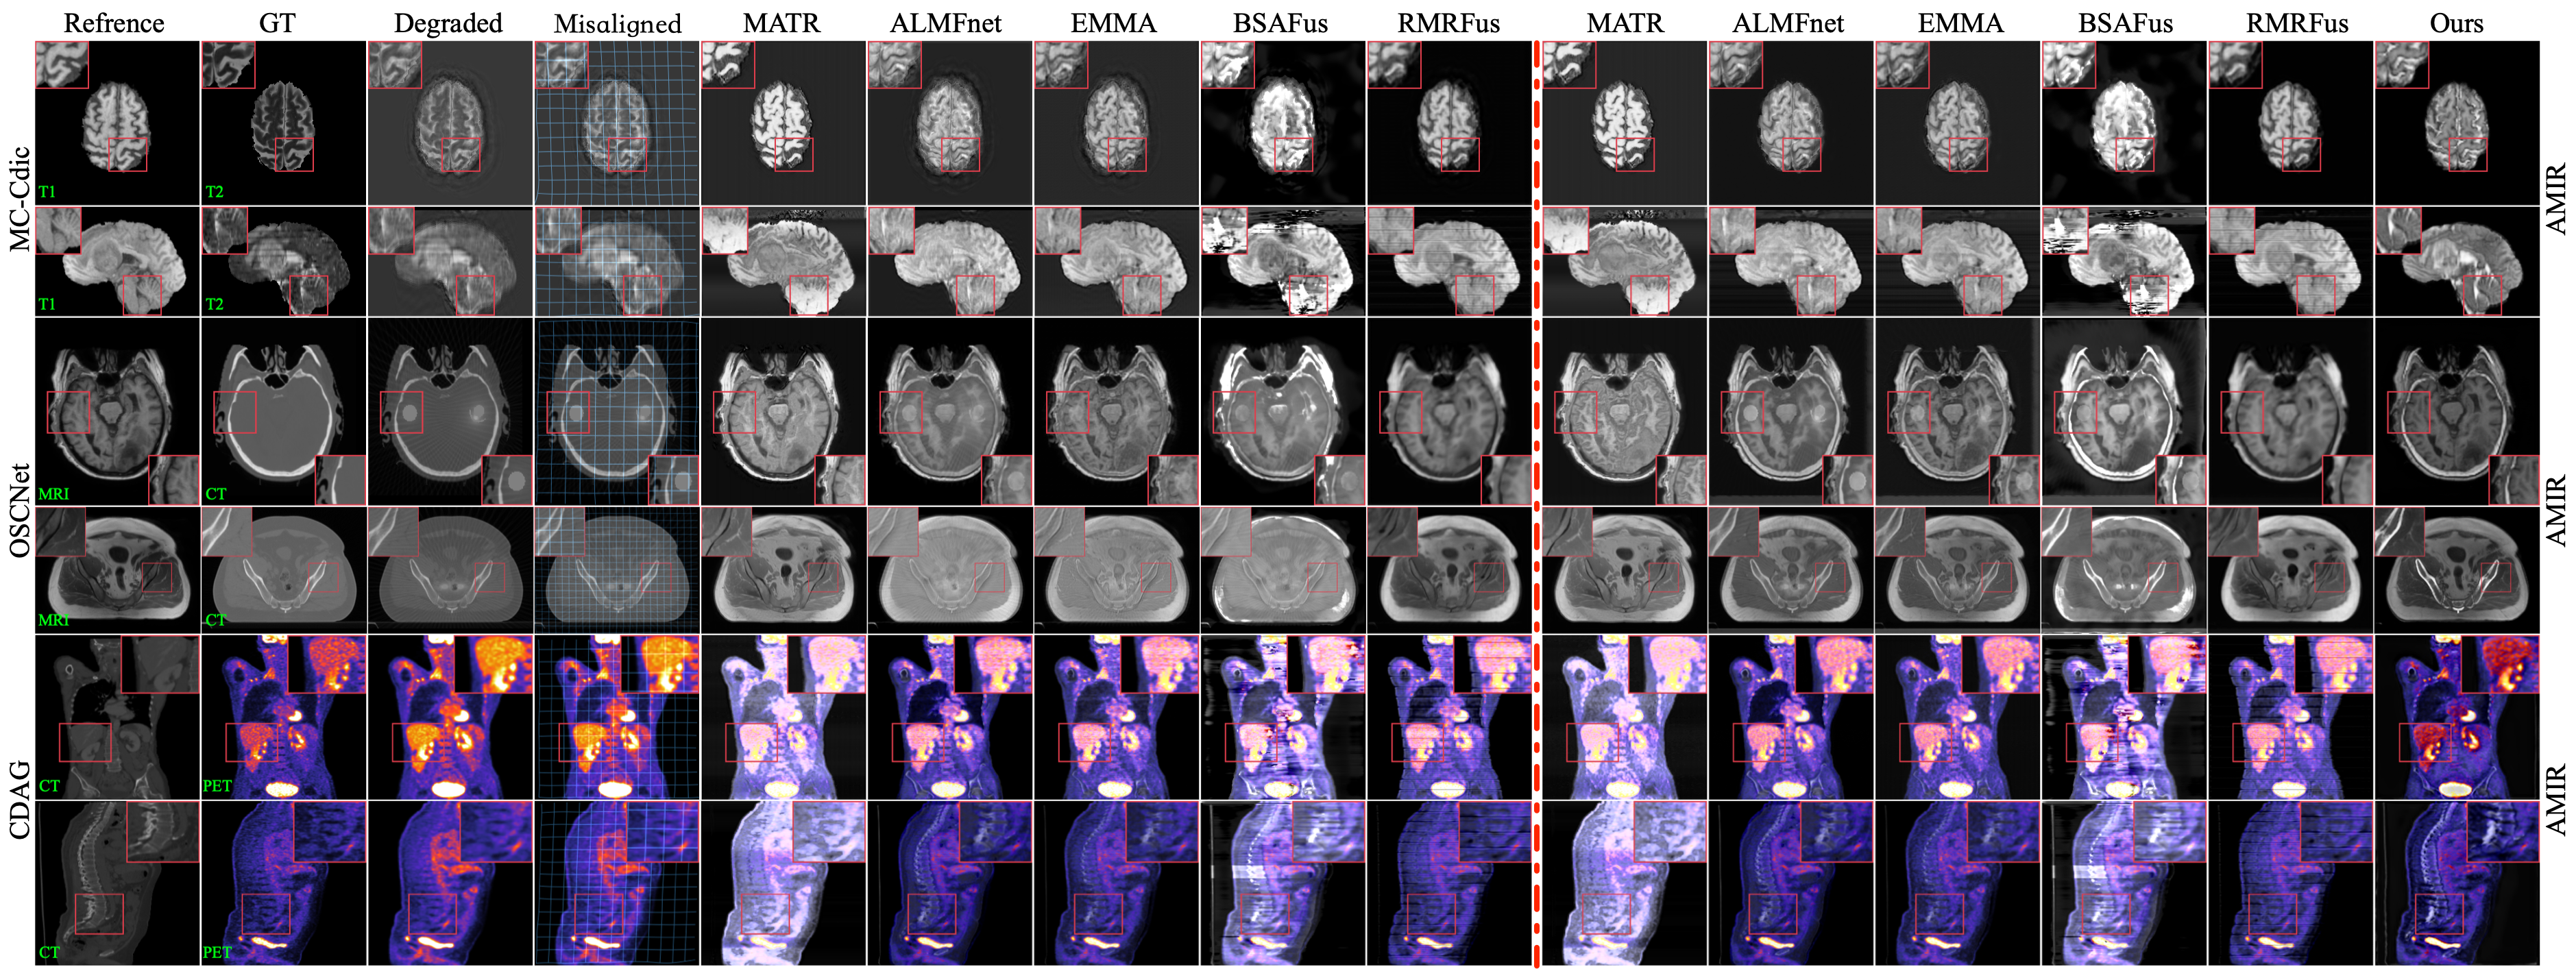

Refer to caption

Figure 4: Visual Comparison of Fusion Results. The first column shows reference images without degradation, and the second column shows high-quality labels. The third and fourth columns present misaligned degraded images and their distortions. Columns 5 to 15 display results from different fusion methods. The image restoration methods to the right of the red line are shown on the right side of the figure, while those to the left are shown on the left side.

Comparison of Results on BraTS2020. The MRI-T2 imaging process is often time-consuming, during which slight patient movement may introduce inevitable motion artifacts. To assess our method’s performance in image fusion when source images contain motion artifacts, we compare it against a multi-stage combination strategy on the BraTs2020 dataset. For the comparison method, we first restore the degraded MRI-T2 images using MC-CDic and AMIR, respectively. Next, we align the restored images with MRI-T1 images using CorrMLP. Finally, we apply five image fusion techniques to generate the final fused images. The top two rows of Figure 4 present the fusion results of different methods. It can be observed that our method demonstrates significant advantages in spatial alignment, motion artifact elimination, contrast enhancement, and detail preservation. Table 1 presents a quantitative comparison of each method’s performance on the dataset. The results indicate that our method achieves the highest average score on all five fusion metrics while significantly reducing computational cost compared to other methods.

Comparison of Results on SynthRAD2023. Metal implants or foreign objects are commonly found in patients, which inevitably introduce metal artifacts in CT images, degrading fusion quality. To assess our method’s fusion performance on images degraded by metal artifacts, we performed comparisons on the SynthRAD2023 dataset. Specifically, we first restored the CT images affected by metal artifacts using OSCNet and AMIR. Then, following the same processing pipeline as for the BraTs2020 dataset, we employed CorrMLP for image registration. Finally, we applied five fusion methods to generate the final fused images. The third and fourth rows of Figure 4 illustrate the visual fusion results of each method on this dataset. As observed, our method effectively preserves structural integrity and contrast while mitigating feature mismatches and metal artifacts. Table 2 presents a quantitative comparison, showing that our method outperforms all others across all metrics while maintaining significantly lower computational cost.

Comparison of Results on FDG-PET/CT. To reduce radiation exposure in PET imaging, low-dose PET images often suffer from noise. To assess our method’s fusion performance on noisy PET images, we compared it with multi-stage approaches. Specifically, we first restored the degraded PET images using CDAG and AMIR, then performed registration and fusion following the same procedure as for the previous datasets. The fifth and sixth rows of Figure 4 present a visual comparison of different methods on this dataset, showing that our method significantly outperforms others in color restoration, noise reduction, feature alignment, and contrast enhancement. Table 3 provides a quantitative evaluation on the FDG-PET/CT dataset, showing that our method achieves the best performance across all metrics. More experimental results are provided in the supplementary material.